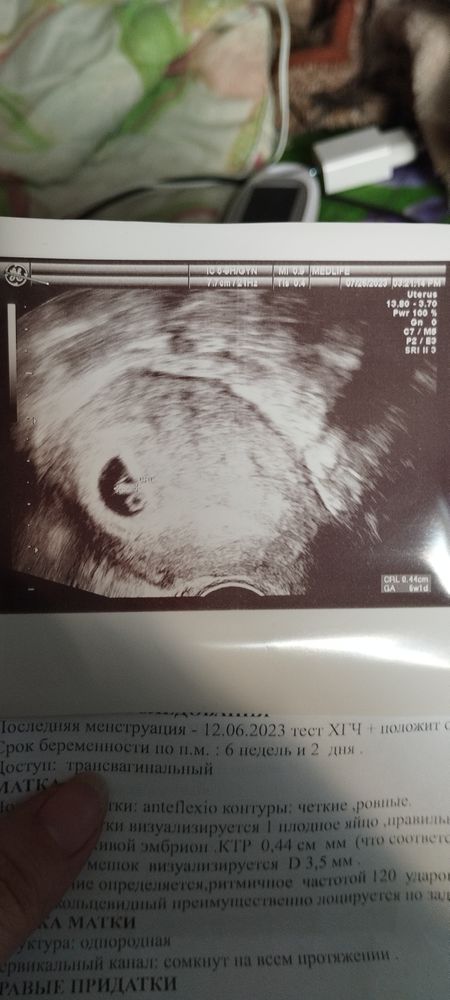

УЗИ, КТГ, доплерДевочки, подскажите, пожалуйста. Сдала ХГЧ 10.07 - результат 93, 12.07 - результат 226, 24.07 - результат 16165 ( это больше чем удвоение каждые два дня) начала сомневаться - вдруг двойня? У мужа по линии есть близнецы. Пошла на УЗИ, врач сообщил что у меня 1 плодное яйцо, всё хорошо, есть сердцебиение, сказала сделать контроль через две недели.

Но когда в конце приема я увидела фото - у меня всё так же остаётся вопрос... Один малыш или два? Что за второй кружочек рядом, может ли быть такое, что врач не увидела двойню или один развивается а второй нет, опасно ли это для малыша? Поделитесь опытом, вся извелась(( Может ли быть такое что через пару недель появится на УЗИ второй эмбрион или нет?

Рядом желточный мешочек, рост обычный на 1 малыша

Если на УЗИ одно плодное яйцо, один желточный мешочек и 1 эмбрион, скорее всего, один малыш и есть.